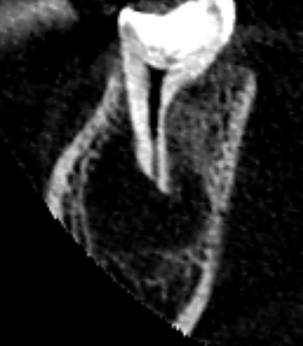

当医院は、保存治療専門の歯科医院です。精密根管治療により根管の感染を徹底的に除去し、膿の改善をはかりました。画像は、根管充填時のレントゲン写真です。雨樋状に根管を清掃し、根の先までしっかり根管充填しました。